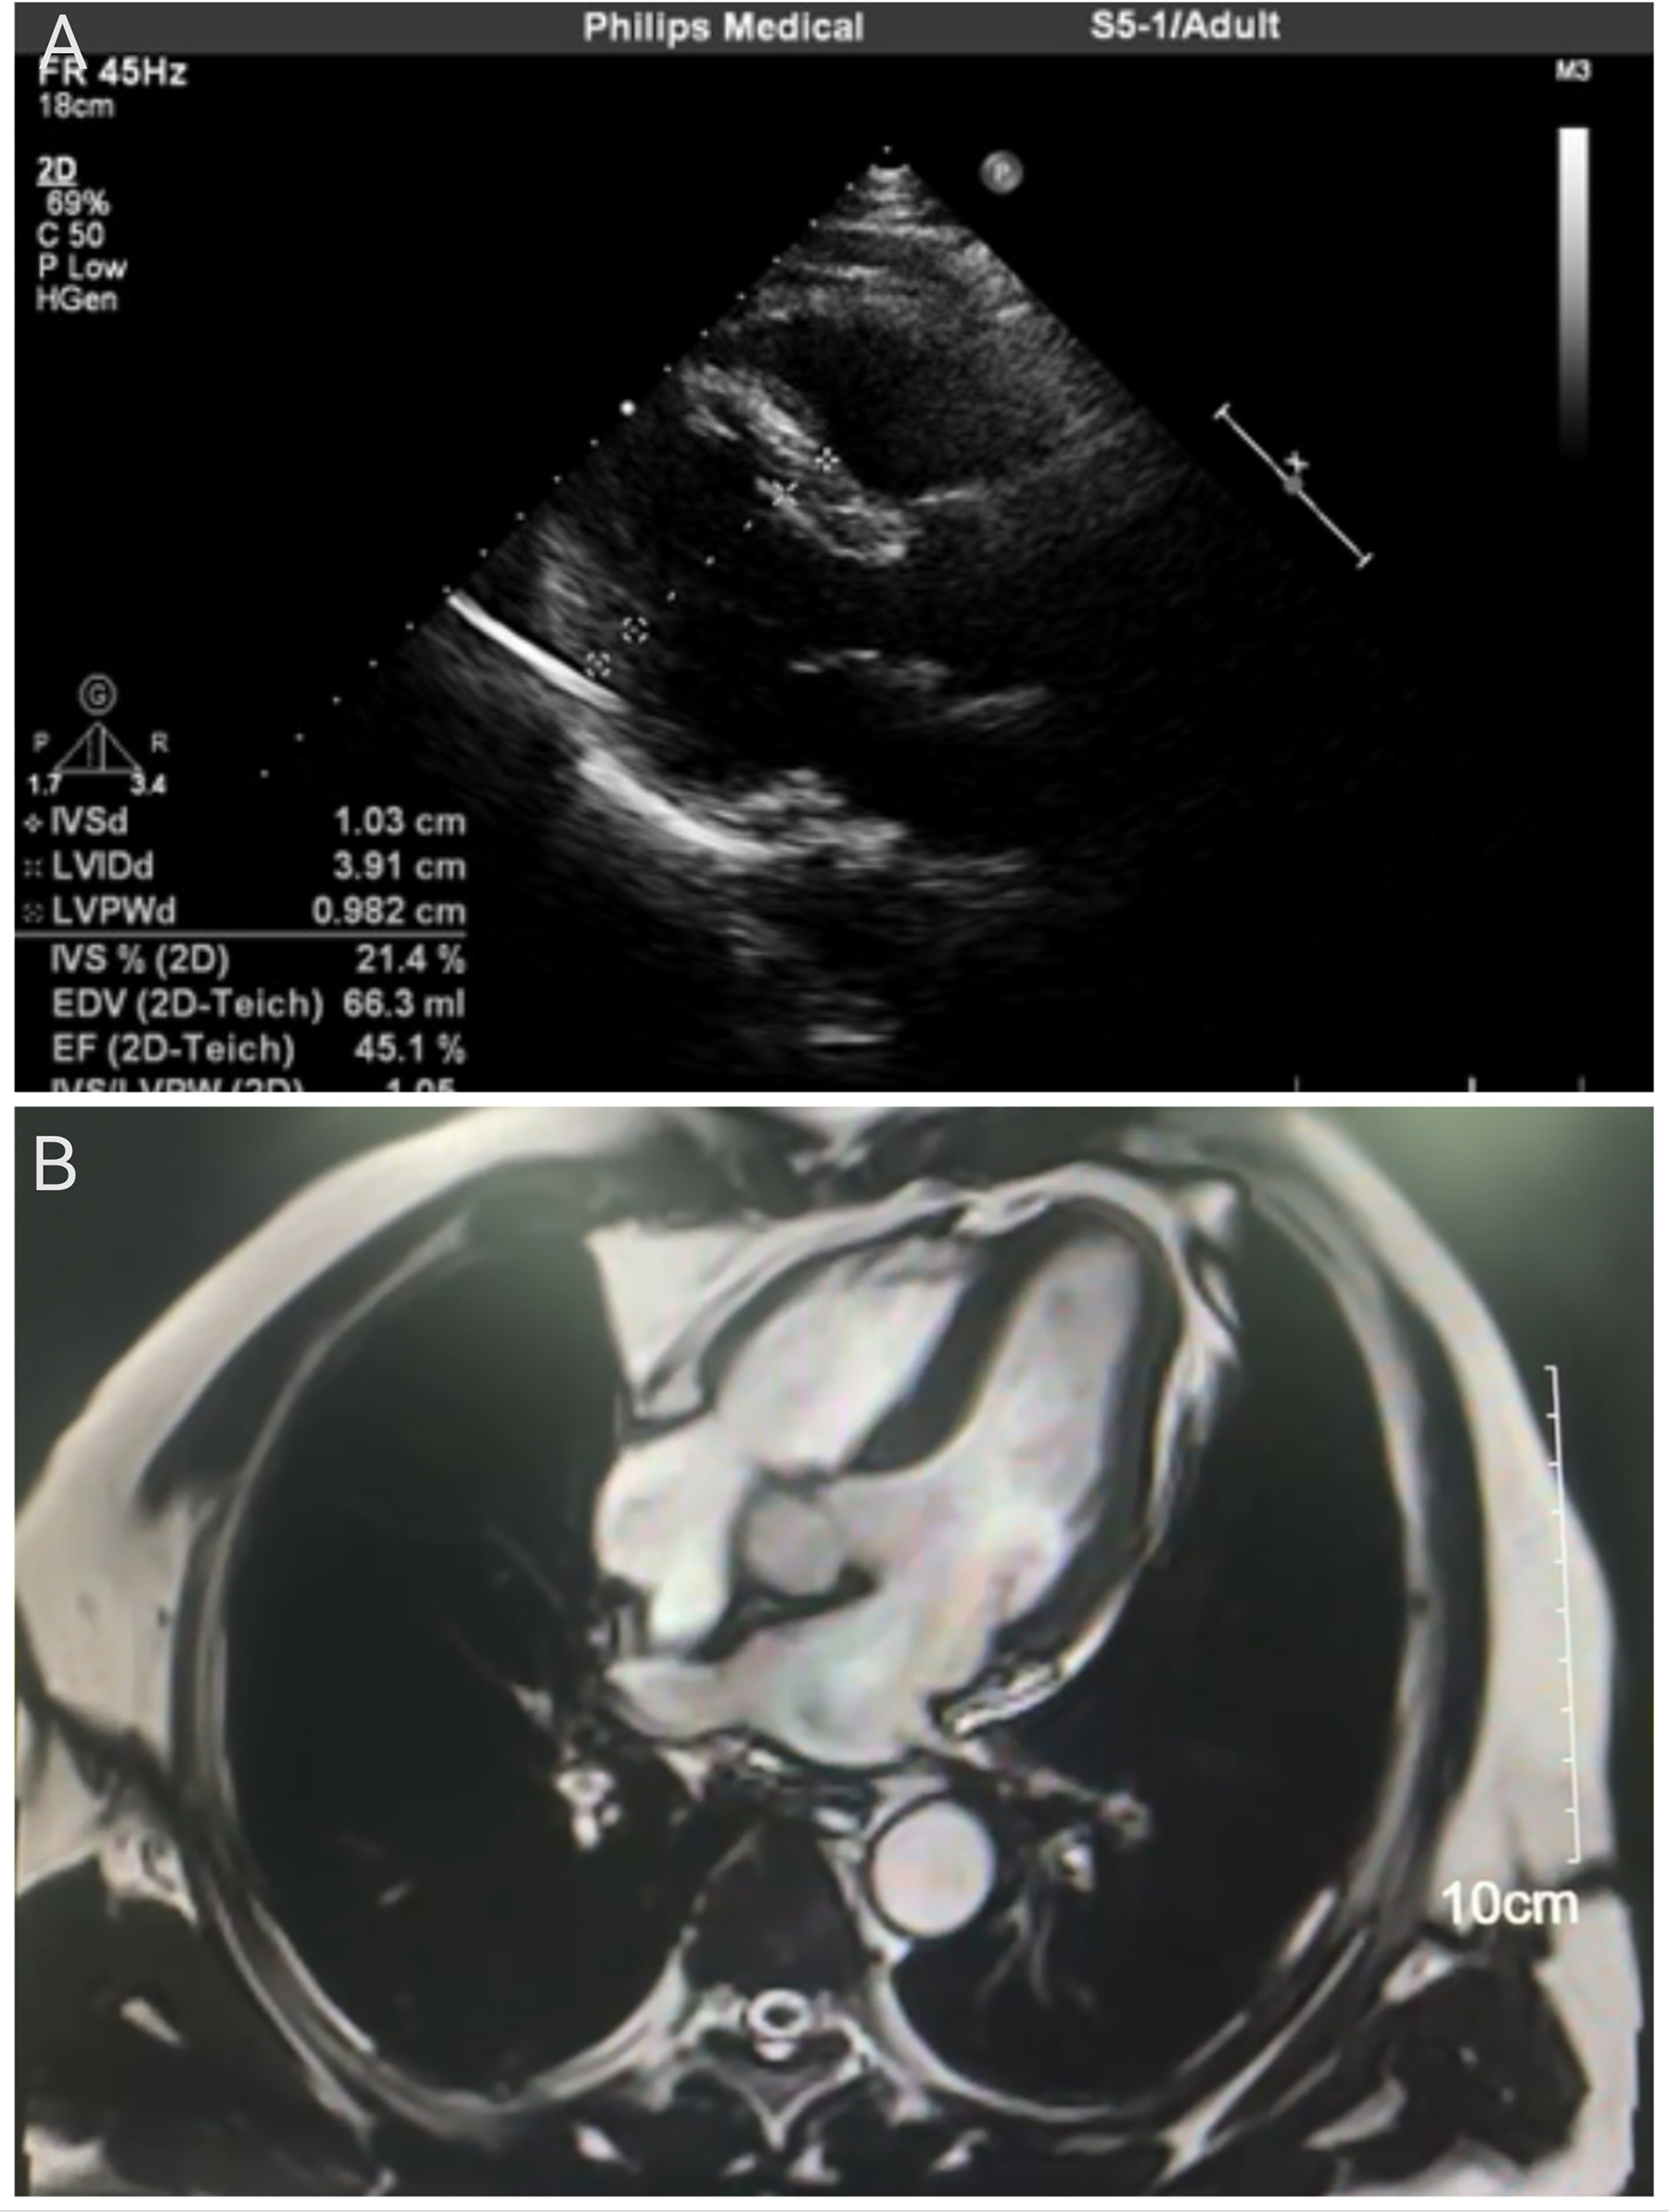

A comprehensive diagnostic evaluation was performed. Transthoracic echocardiography (Figure 2A) showed a structurally normal heart with a left ventricular ejection fraction (LVEF) of 45.1% and globally reduced systolic function in the absence of regional wall motion abnormalities. Cardiac MRI with late gadolinium enhancement (Figure 2B) confirmed the absence of myocardial edema, fibrosis, or any other structural pathology. Coronary angiography (Figure 3) revealed no evidence of stenosis. An acetylcholine challenge test was negative for coronary vasospasm. Toxicological screening was negative for common QT interval-prolonging medications and for a comprehensive panel of illicit substances (cocaine, amphetamines, cannabinoids, opioids).

Figure 2

Cardiac imaging assessments. (A) Transthoracic echocardiogram (parasternal long-axis view) indicating a structurally normal heart. Quantitative measurements are displayed, including a left ventricular ejection fraction (LVEF) of 45.1%. (B) Cardiac magnetic resonance image (four-chamber view) with late gadolinium enhancement. The homogeneous myocardial signal and the scale bar (10 cm) confirm the absence of edema, fibrosis, or structural abnormalities.